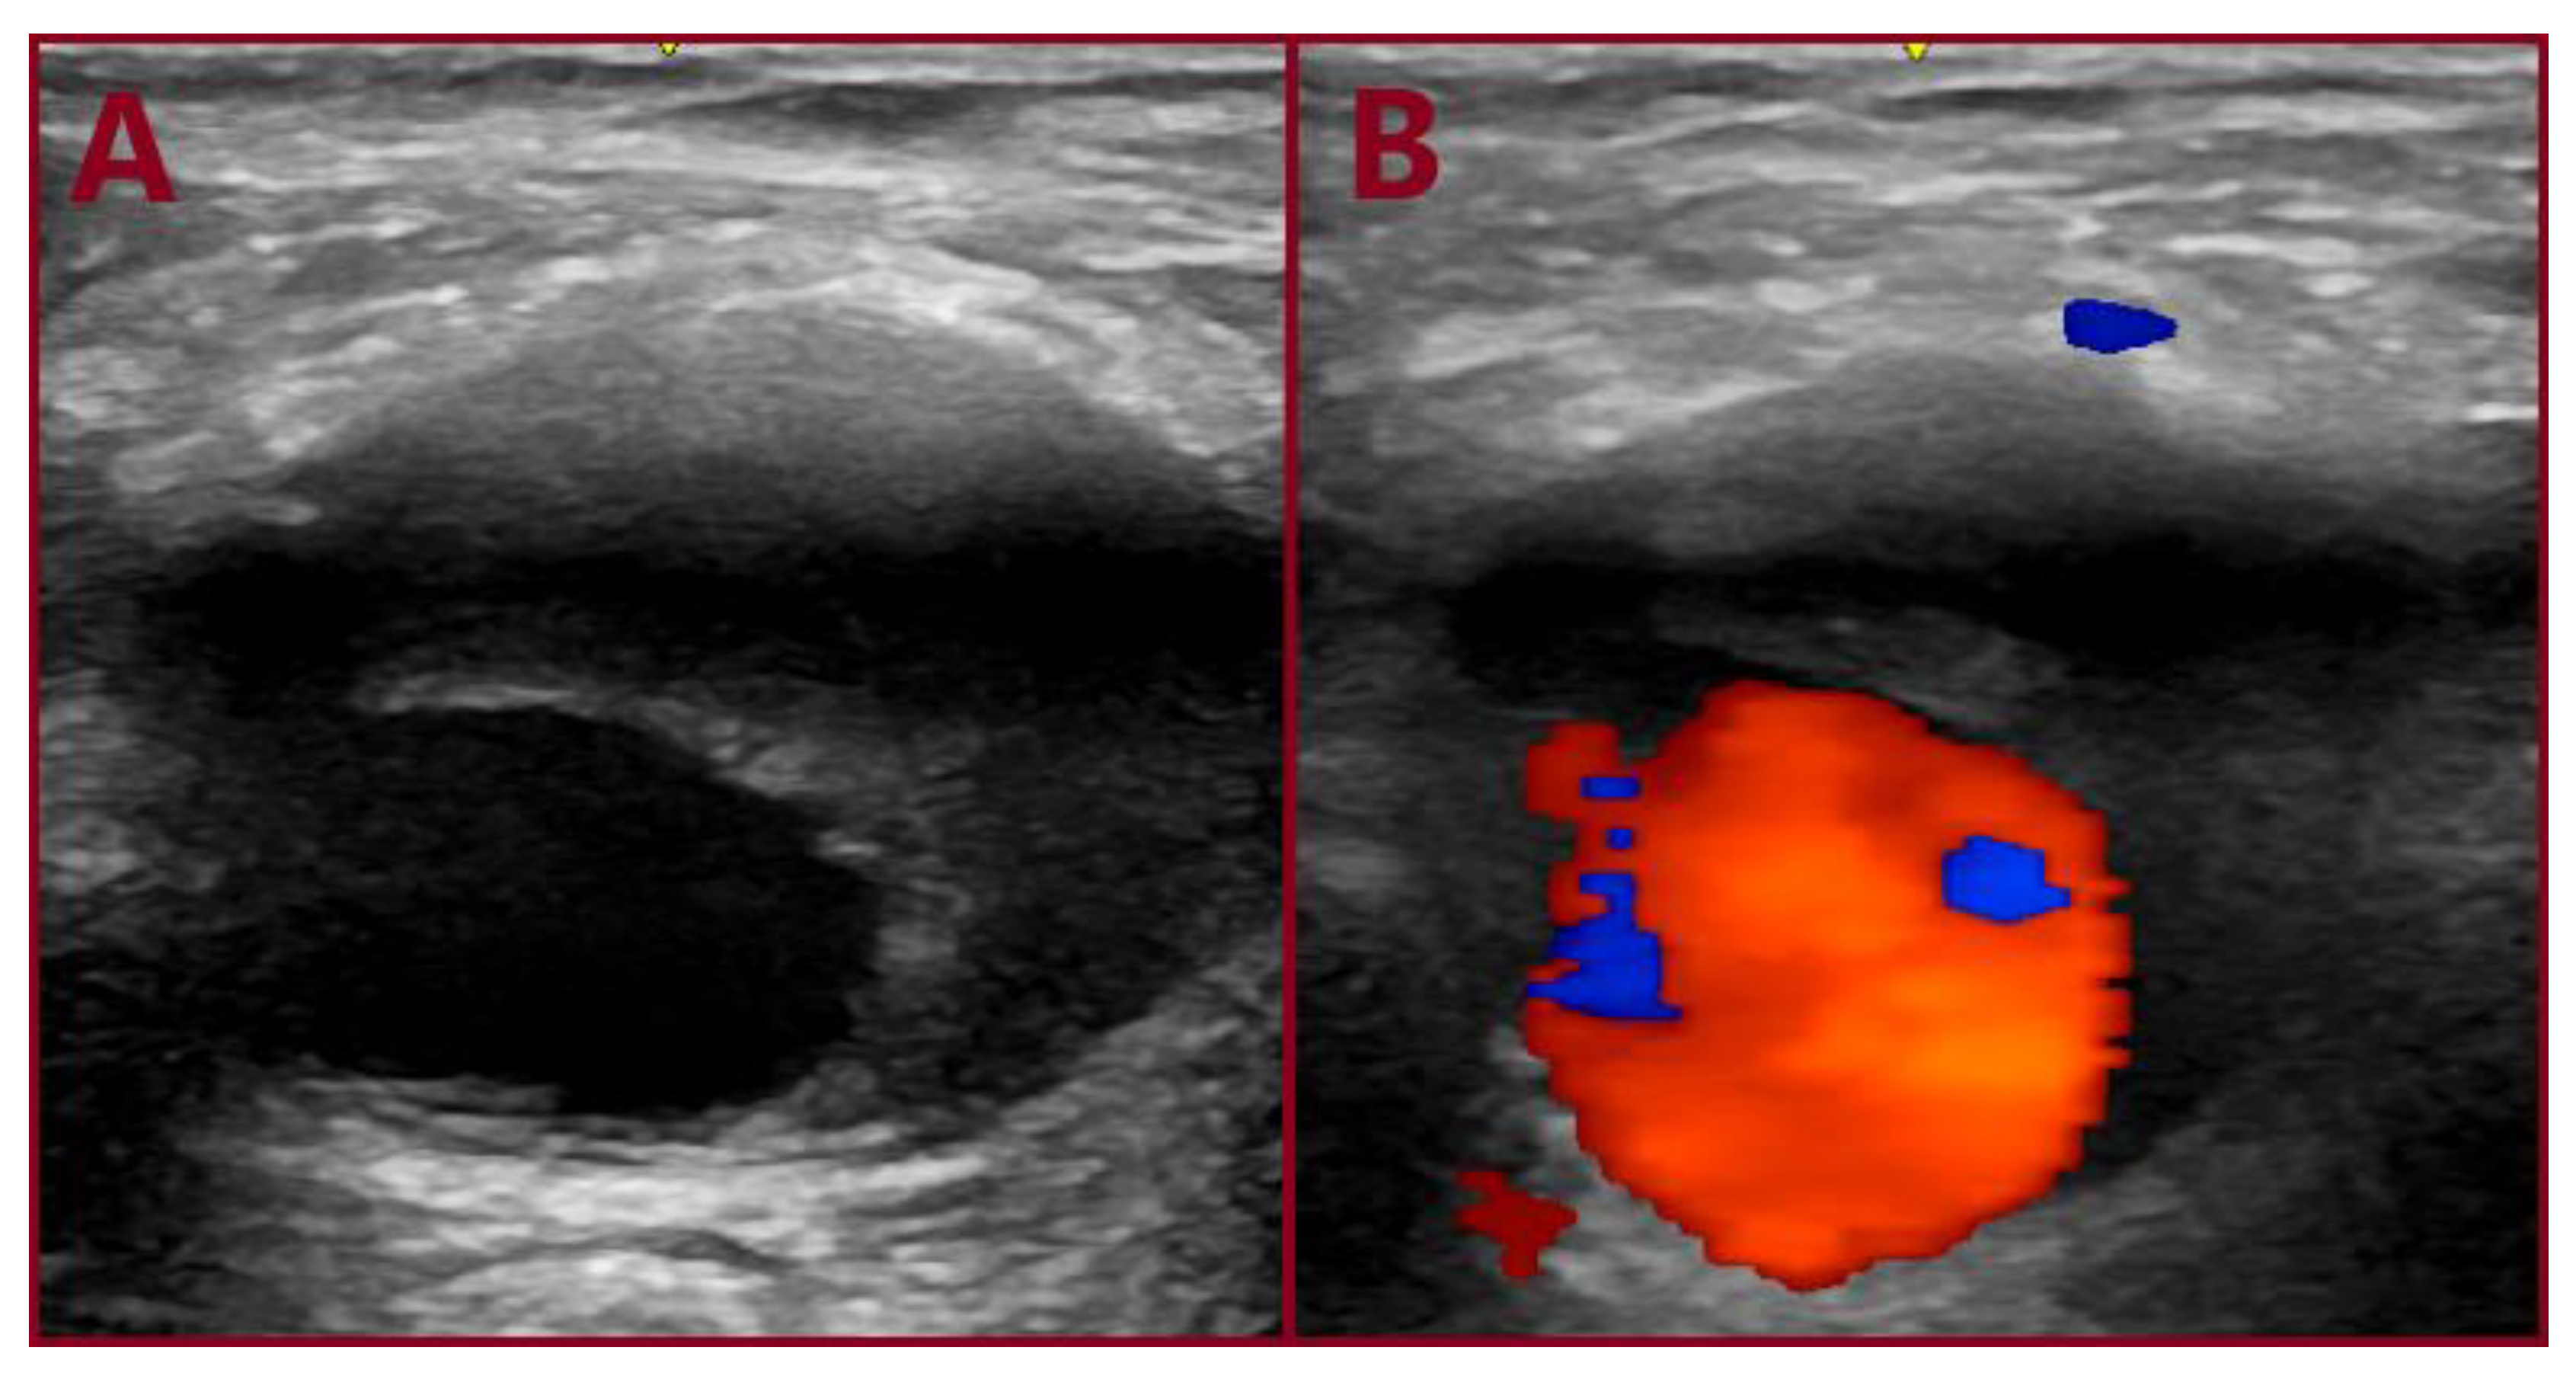

3.1. Case 1

3.2. Case 2

3.3. Case 3